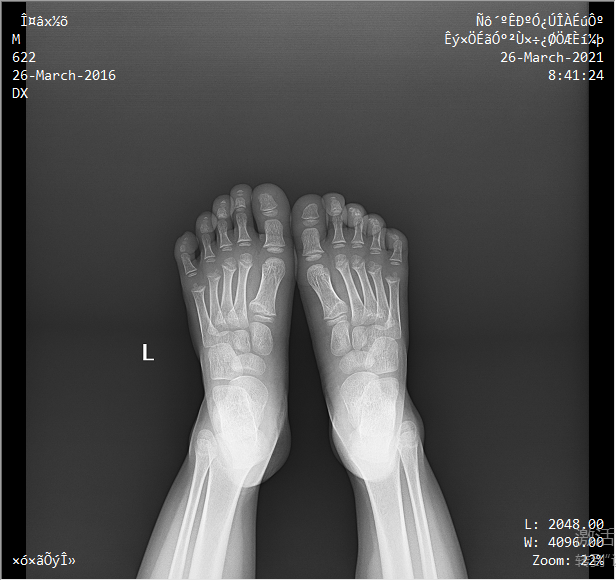

采用靈活的懸吊式機(jī)架設(shè)計,配置電動升降攝影床/移動床與高品質(zhì)平板探測器,實現(xiàn)圖像與擺位的有機(jī)統(tǒng)一,可應(yīng)用于DR攝影多種臨床X線檢查領(lǐng)域。

● 球管運(yùn)動靈活

球管上下升降范圍大,便于站立位時足踝負(fù)重狀態(tài)下的檢查。

依據(jù)臨床圖像庫自動進(jìn)行圖像后處理,呈現(xiàn)效果佳。